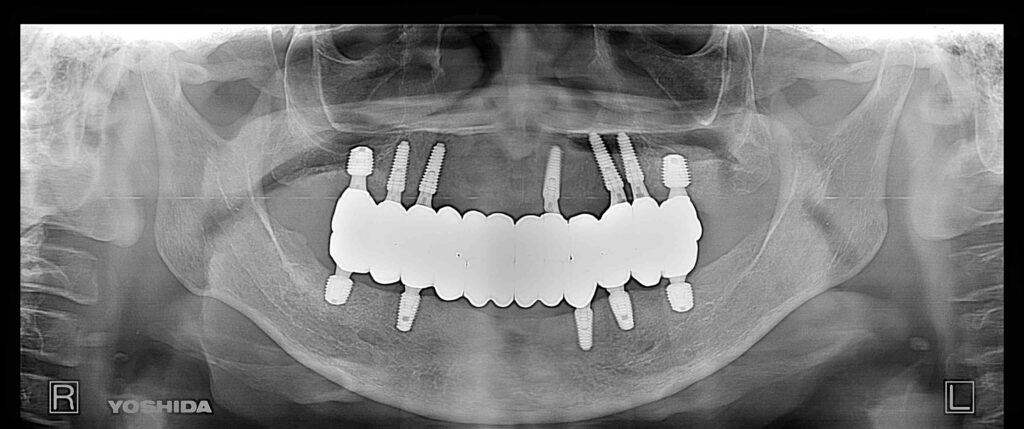

症例550代 男性 主訴 奥歯がグラグラで噛めない

治療前

治療後

しっかり噛めるようになりたい、入れ歯だけは絶対に避けたいと強い訴えがあり、固定制のインプラントを提案。上顎7本、下顎2本、口腔内全体で9本インプラントを埋入。

免荷期間中は、QOLを損なわない為に、暫間インプラント(即時荷重)を埋入、オペ当日に仮歯を装着し、咀嚼可能にした。上顎はAGC(Auro Galvano Conuscrown)ジルコニアブリッジを装着。

治療期間は約5ヶ月間を要した。

リスクとしては外科的侵襲がある。デメリットは、保険外診療の為、経済的負担がある。

費用 628万(税込)(オペ・仮歯・最終補綴物まで含む)